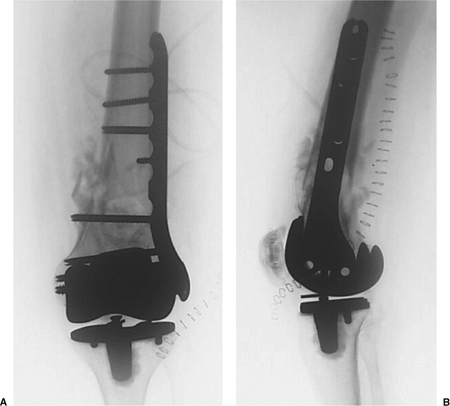

![]() |

|

Figure 45.4. AP (A) and lateral (B) radiographs of final revision construct with long-stem implant, struts, and multiple Luque wires.

Figure 45.11. AP (A) and lateral (B)

radiographs depicting the final construct with locking, distal, femur plate with proximal, unicortical, locking screws through one cortex and the cement mantle. |